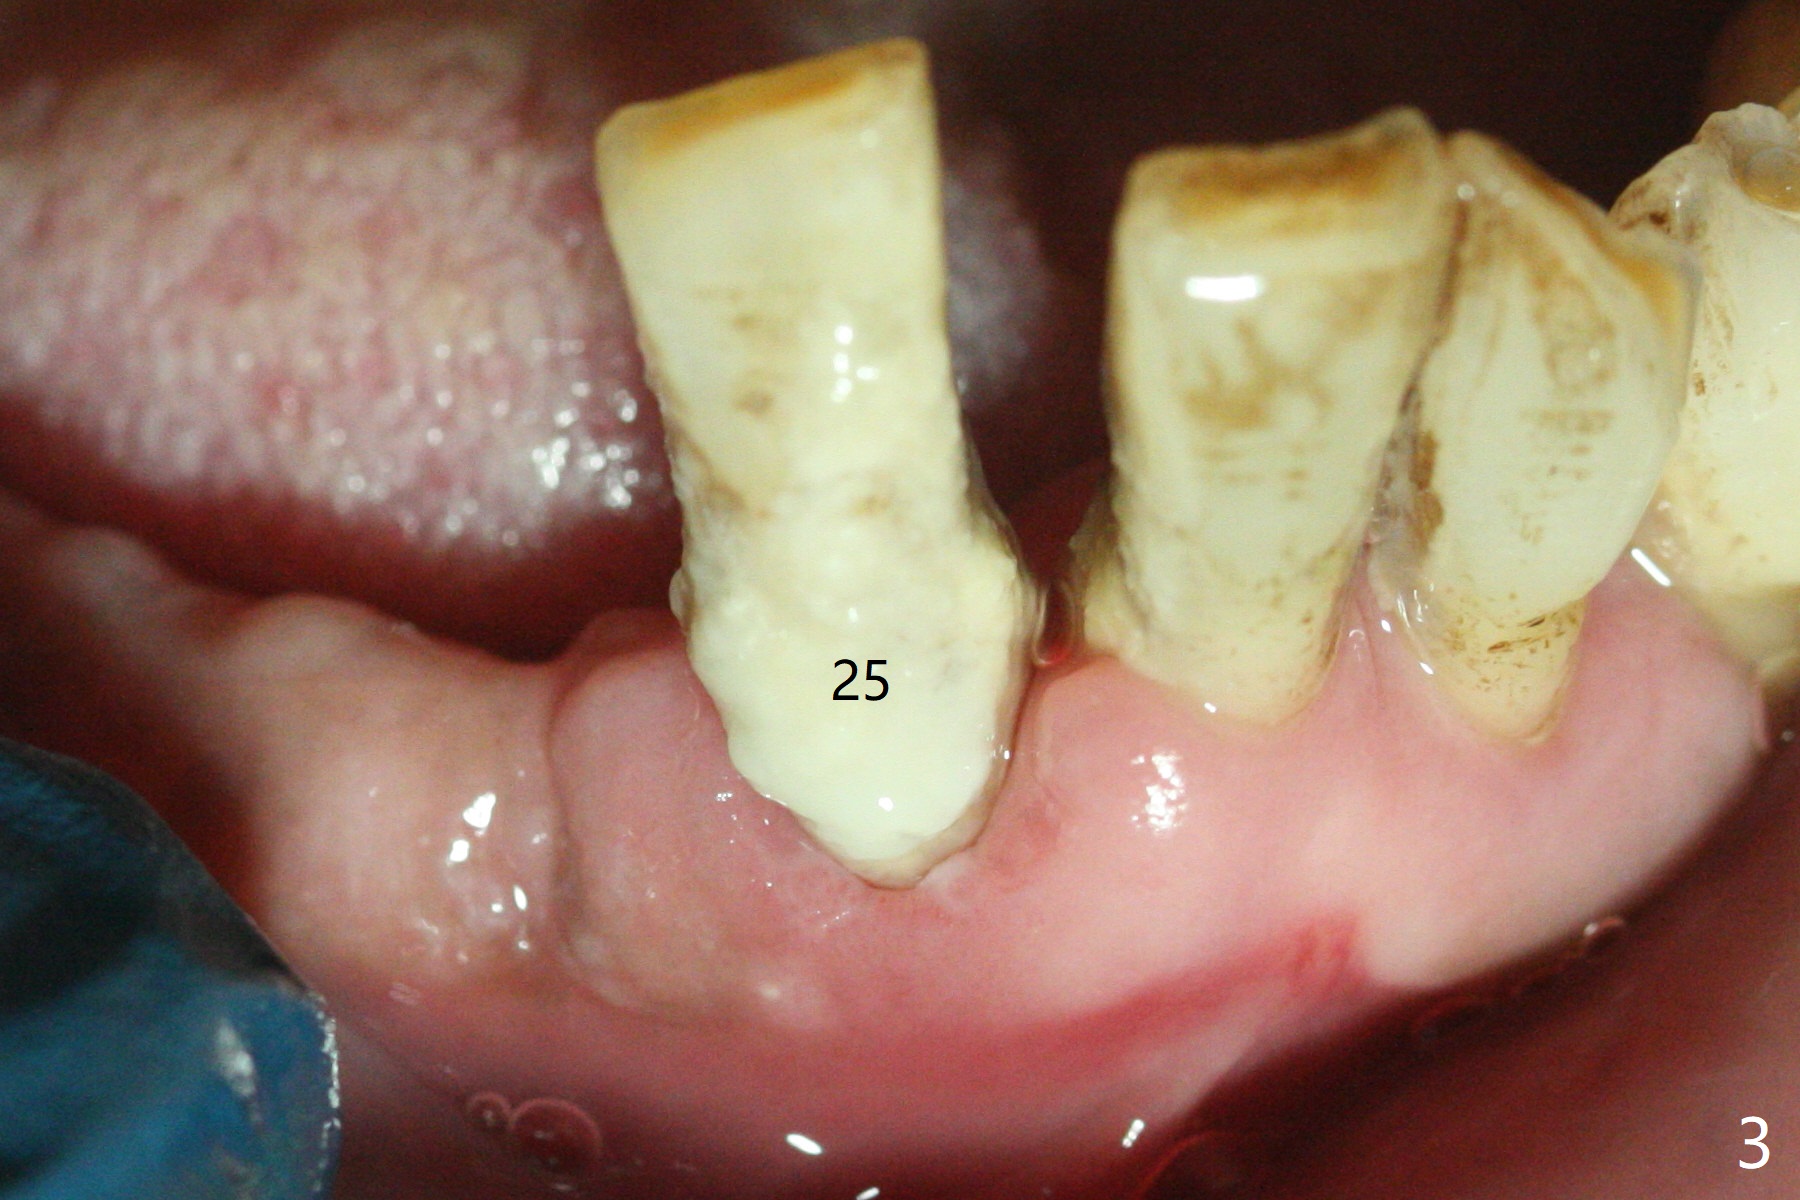

The 58-year-old man returns for #25 extraction while the redo implant at #12 is osteointegrating (Fig.1-3). After discussion, he agrees with socket preservation with 8x8 mm BioXclude (Fig.4 * (4-0 PGA)) and Vanilla graft (Fig.5 *). The socket is healing 6 days postop (Fig.6).